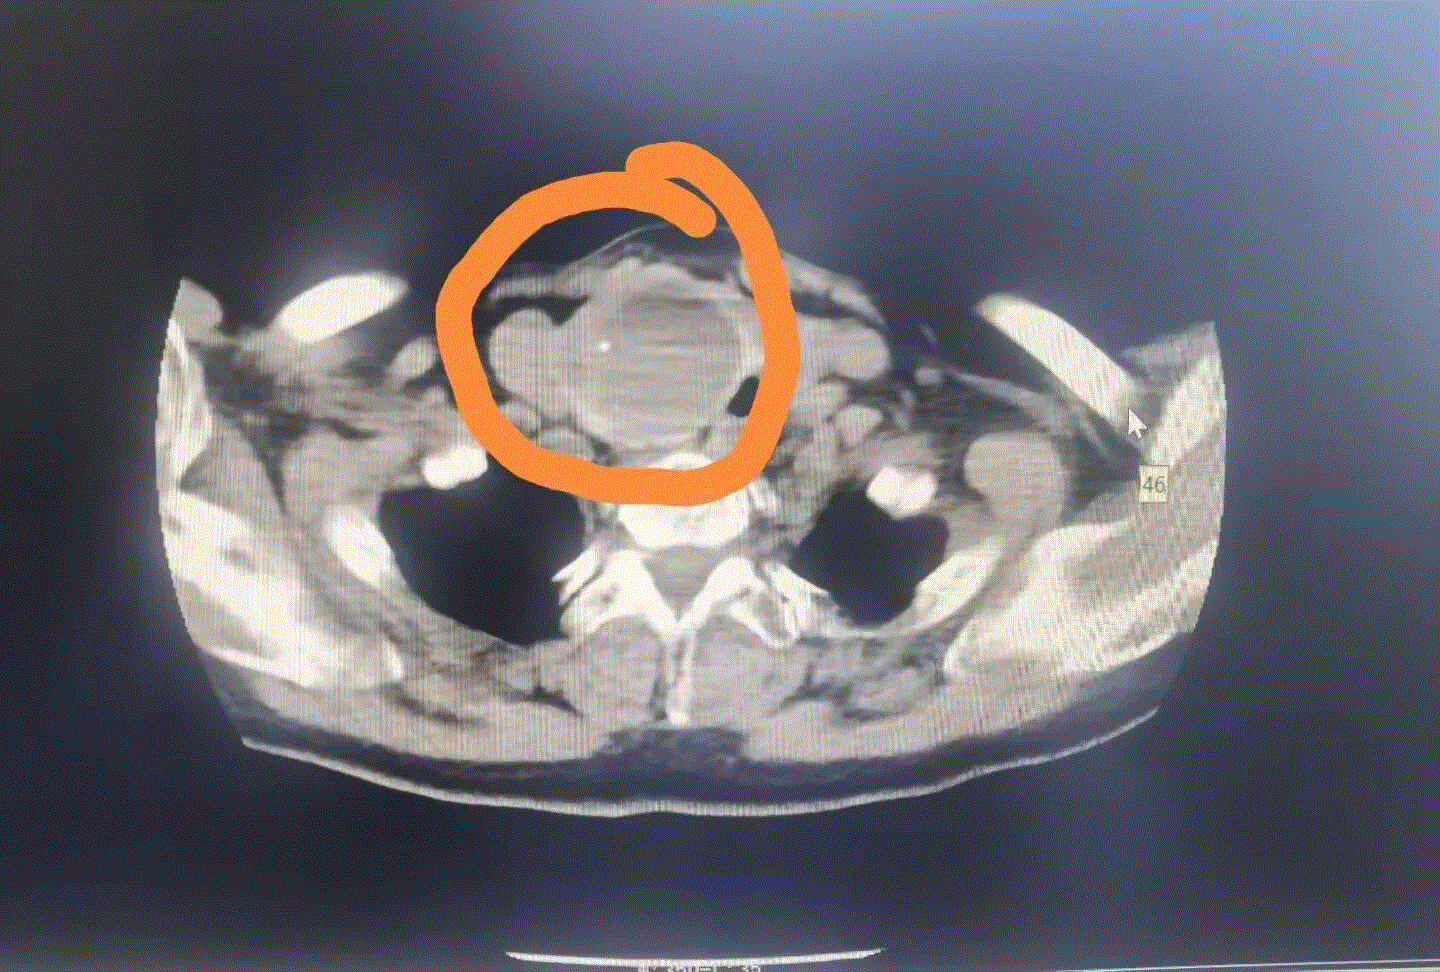

手术当天,真正的挑战才刚刚开始——李阿姨右侧甲状腺肿物大小约5.0cm×7.0cm(约鸡蛋大小),左侧肿物也有4.0cm×3.0cm,两个肿物挤在本就狭窄的颈部空间,给手术操作带来了极大挑战。